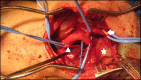

Abstract: A carotid body tumor is a rare neoplasm, generally benign, that predominantly affects people between their fourth and fifth decades of life. It manifests as a pulsatile and generally painless cervical mass with firm consistency, located below the angle of the jaw. It can progress to the extent that it causes localized pain, dysphagia, hiccups, hoarseness and hypersensitive carotid body syndrome. This article reports the cases of two female patients diagnosed with this tumor who were treated surgically. The first was treated with block resection of the tumor, while the second patient, who had an early stage tumor, was treated with subadventitial resection of the lesion.

O tumor de corpo carotídeo é uma neoplasia rara, geralmente benigna, que acomete, sobretudo, indivíduos entre a quarta e a quinta décadas de vida. Manifesta-se pela presença de massa cervical consistente localizada abaixo do ângulo da mandíbula, pulsátil e comumente indolor. Pode evoluir para dor local, disfagia, soluços, rouquidão e síndrome do corpo carotídeo hipersensível. Este artigo relata os casos de duas pacientes diagnosticadas com essa neoplasia e submetidas ao tratamento cirúrgico. A primeira foi submetida a uma ressecção em bloco do tumor, enquanto a segunda, com estadiamento mais precoce, foi tratada com uma ressecção subadventicial da lesão.